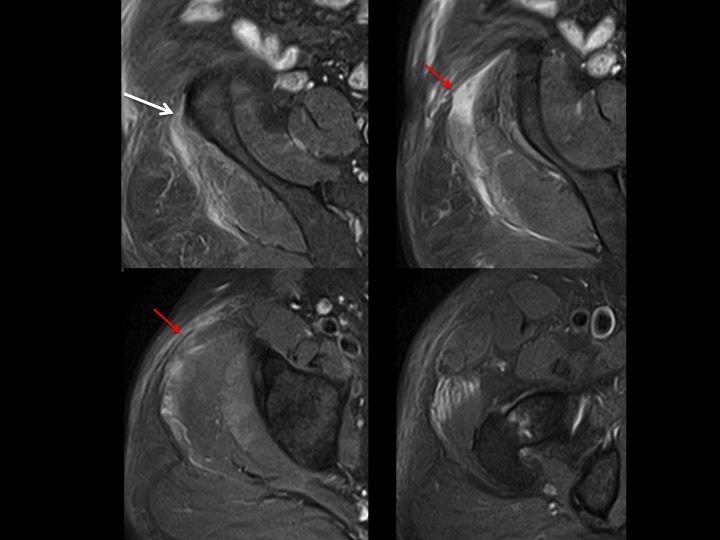

69M 1 week hip pain

There is complete retracted avulsion of proximal iliotibial band at its iliac tubercle origin, with contiguous delaminating tear of the gluteus medius fascia, subfascial hemorrhage and low grade G medius muscle strain. I have only ever seen proximal ITB tears in women, with few non-insertional tears and gluteal fascial tears more common (in my experience) in men. This man has a history of diabetes. I dont know if he had trauma.